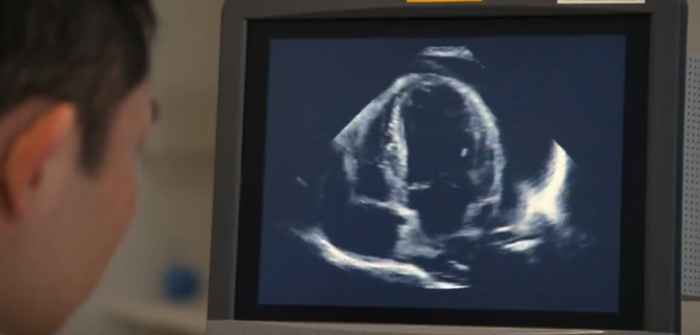

图 | 视觉中国